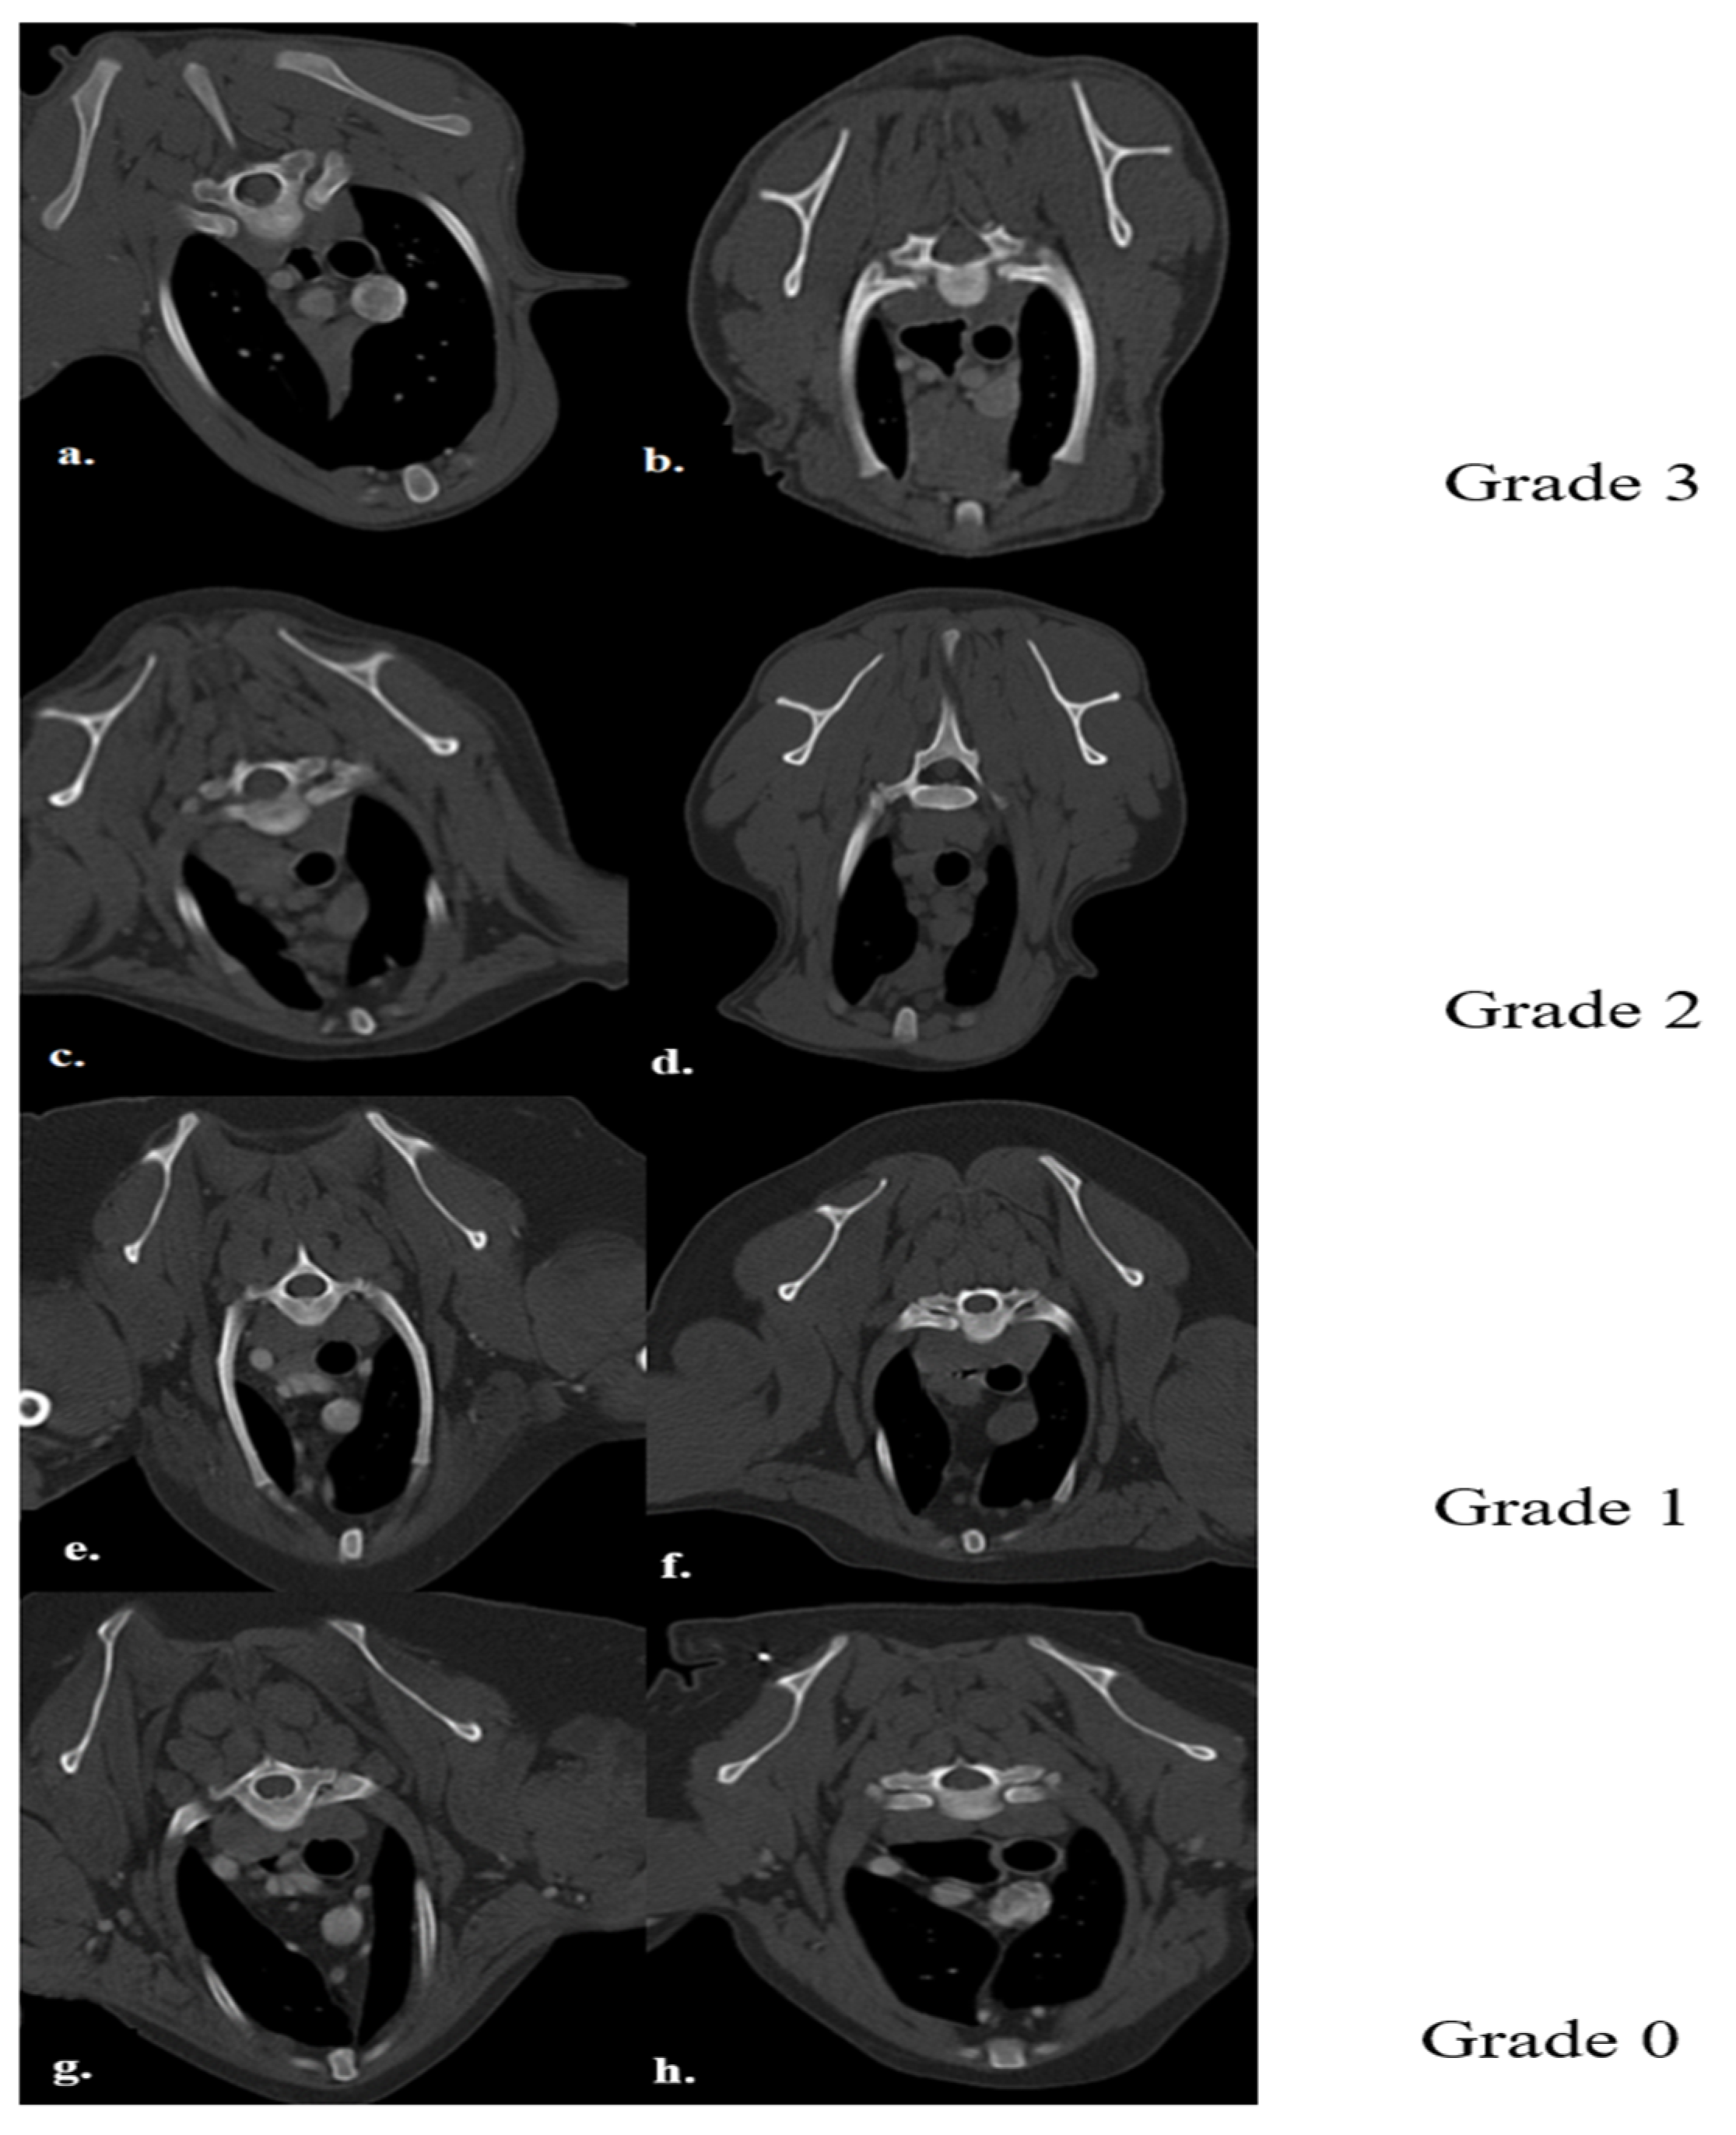

The thymus glands were evaluated in the first step to determine whether they were visible or not. Non-visible thymus glands were those with complete degeneration seen with fat attenuation and not distinguishable from mediastinal fat. After that, a grading system for thymic tissue appearance was used based on its predominant component (grade-0: totally fatty replacement of the thymus (non-visible) and could not differentiate from mediastinal fat; grade-1: more than 50% fatty replacement of the thymus; grade-2: more than 50% soft tissue component in the thymus; grade-3: totally soft tissue component in the thymus (Figure 1). After grading the thymus, the attenuation (CT number) of thymic tissue in plain and contrast-enhanced images was measured. For this purpose, a round-shape region of interest (ROI) with a surface equal to 75 mm2 was considered in the widest part of the organ for large thymus glands (Figure 2) and a smaller ROI for small thymus glands. Then pre- and post-contrast Hounsfield Units (HU) were compared for each patient individually and also between groups for evaluating the pattern of attenuation alteration.

Figure 1. Demonstration of Post-contrast Transverse CT scan images for Different Grades of Thymus. Picture (a) shows a Visible Grade-3 Wedge-shape Left-sided Thymus in a 4-month-old Male Mixed-breed dog. Picture (b) shows a Visible Grade-3 Rectangular-shape Midline Thymus in a 5-month-old Female Shih Tzu Dog. Picture (c) shows a Visible Grade-2 Wedge-shape midline Thymus in an 8-month-old Male Spitz Dog. Picture (d) shows a Visible Grade-2 Rectangular-shape Midline Thymus in a 3-year-old Female Mixed-breed dog. Picture (e) shows a Visible Grade 1 Wedge-shape Left-sided Thymus in a 6-year-old Female Terrier Dog. Picture (f) shows a Visible Grade-1 Rectangular-shape Midline Thymus in a 7-year-old Female Terrier Dog. Picture (g) shows a non-visible Grade-0 Wedge-shape midline Thymus in an 11-year-old Female Shih Tzu Dog. Picture (h) shows a Non-visible Grade-0 Linear-shaped midline Thymus in a 6-year-old Female Cocker-Spaniel Dog.